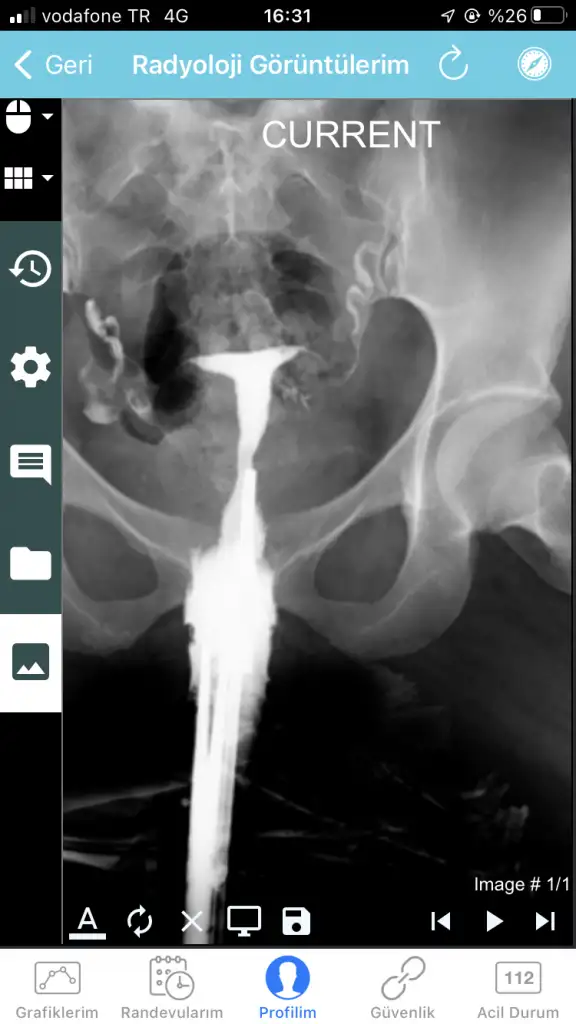

Kızlar merhaba, bugün Hsg çektirdim. Görüntülerine bakabilir misiniz tecrübeli arkadaşlar

İlk yorumu yapan olmadı mı çekimden sonra🙃 T görünümü var ama raporda şekil bozukluğu ile ilgili bir ibare yok. Ancak sol tüpün tıkalı olabilir 🤔 genel bi başlık aç istersen daha çok yazan olur inşallah ben yanlış algılamışımdır

Merhaba , tıkanıklık bu filmde açılabiliyor mu hiç bilmiyorum . Doktor yorum olarak kapalı görünüyor sanki ama ben sıvı geçişini gördüm aslında kapalı değil dedi . Anlamadım . Yani filme baktığımızda ince bir çizgi gibi geçiş var . Doktora göre de var , raporda kapalı olduğu yazıyor .